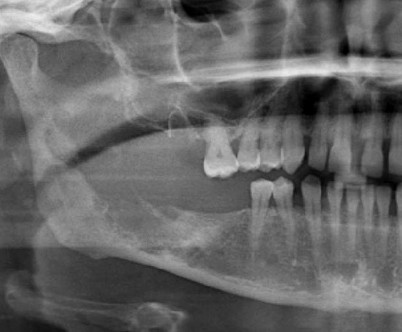

Abb 1 A Panoramaschichtaufnahme Bei Erstvorstellung Osteolyse Download Scientific Diagram

Trauma Spatfolgen Zahnerhalt Durch Dvt Bei Osteolyse Zwp Online Das Nachrichtenportal Fur Die Dentalbranche